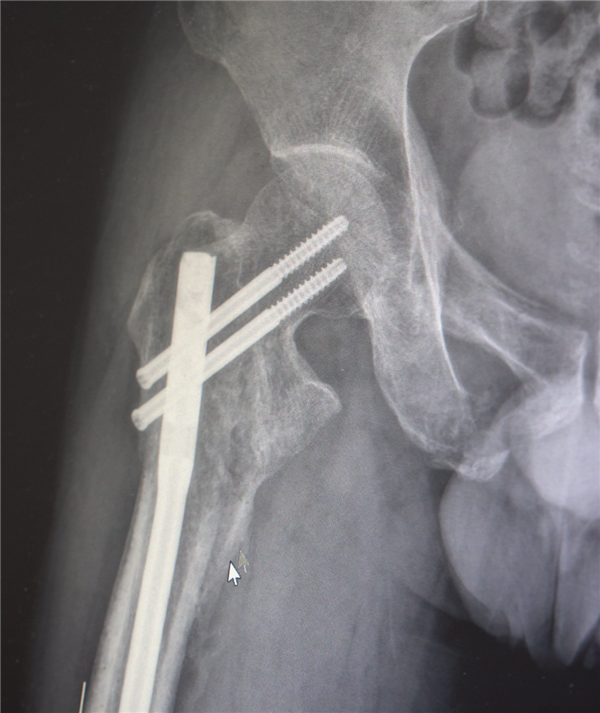

创伤性失血性休克、多发性肋骨骨折、肺部损伤、右侧肩胛骨粉碎骨折、右侧肱骨髁上开放粉碎性骨折、右股骨粗隆及股骨干粉碎性骨折、骨盆粉碎性骨折、腰椎横突多发骨折、腰骶柱神经损伤、臂丛神经损伤、胸腔积液、腹腔积液等。

经医生检查,张先生全身共有六处较大骨折部位,多为严重粉碎性骨折,全身骨折碎块达30多块!

医生随即展开紧急抢救,总算是保住了他的性命,后续转入创伤骨科继续治疗,此时最大的挑战出现了。